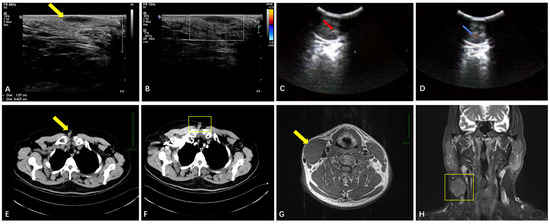

| Soft Tissue | Ultrasound (n = 26) | Well-circumscribed hypoechoic masses (n = 25, 96.1%); sparse blood flow. | Larger size (mean: 93 mm); rare irregular margins. |

| CT (n = 9) | Well-defined hypodense nodules (n = 9, 100%); moderate enhancement | N/A | |

| MRI (n = 4) | T1-hypointense (n = 3, 75%) or T1-isointense (n = 1, 25%); variable T2-signals (hyper-/mixed). | N/A (all benign) | |

| Breasts | Ultrasound (n = 5) | Irregular margins; a non-parallel orientation; posterior shadowing (BI-RADS 4B) (n = 4, 80%) | N/A (all benign) |

| Sellar Region | MRI (n = 4) | T1-isointense; T2-variable (“star-like crack signs” in 50%); heterogeneous enhancement in 50% | N/A (all benign) |